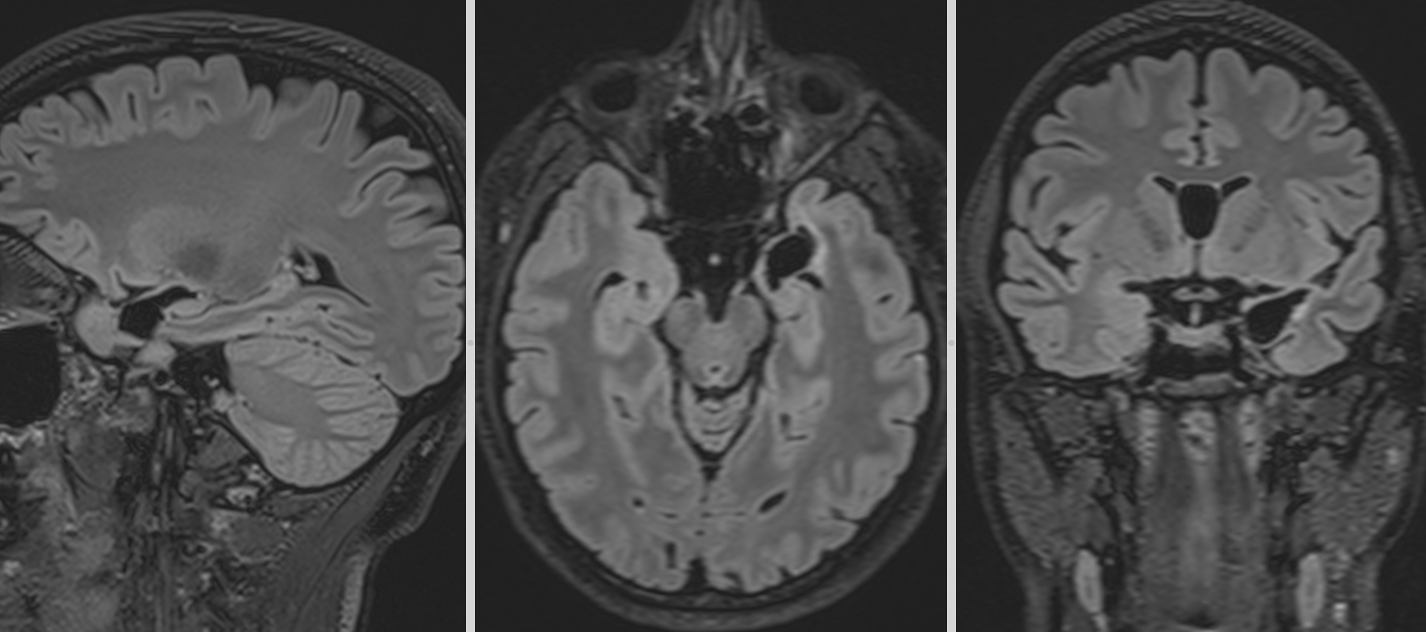

Investigațiile următoare, întâi peste 3 luni apoi peste încă un an au confirmat: nici o urmă de rest sau recidivă tumorală.

La aproape 3 ani de la operație, fără crize epileptice, fără deficite neurologice și cu un RMN curat putem considera că pacienta este vindecată.